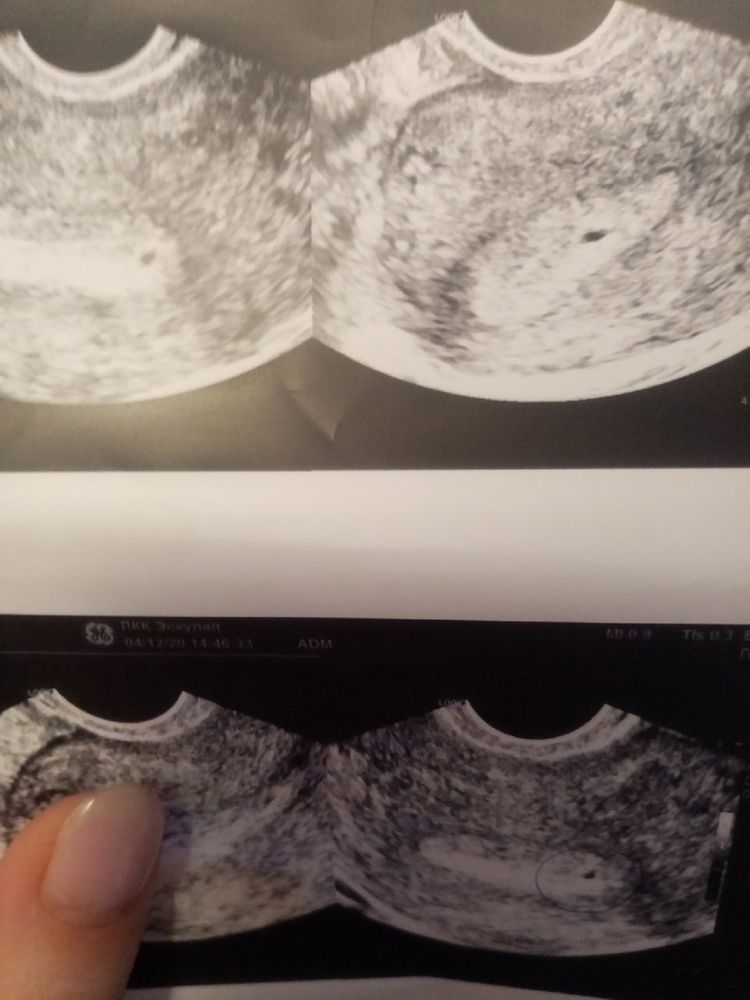

подозрение на плодное яйцо 2мм тесты отр.

и подозрение на плодное яйцо 2мм!

Врач сказала или это узелок на эндометрии и выйдет с месячными или плодное яйцо вырастет.